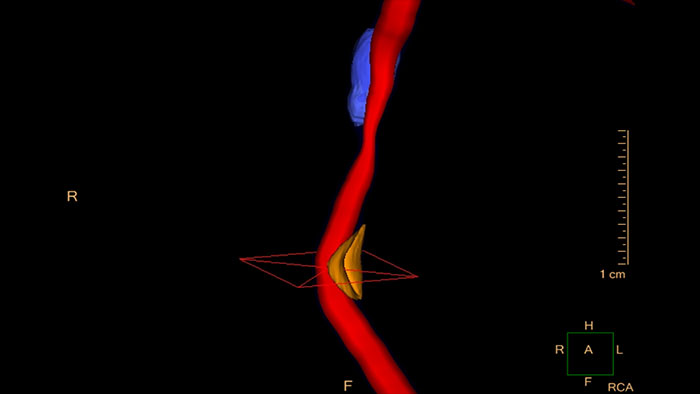

Evaluate coronaries plaque

Enables performing cross-sectional measurements along the coronary arteries, and automatically calculates regional and global quantities of plaque volume.